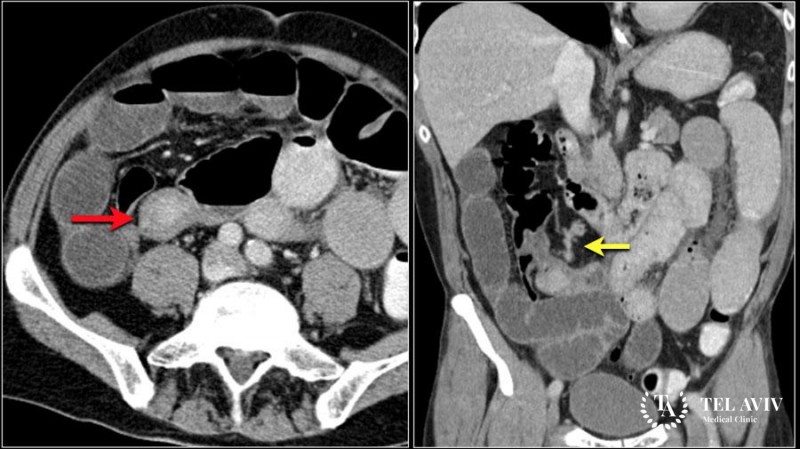

Описание злокачественного образования в пищеводе впервые появилось в 1952 году. Ученые активно исследовали данное направление. Вскоре были обнаружены факторы, подтверждающие опасность новообразования на пищеводе. Низкодифференцированные карциноиды встречаются относительно редко. Существует три формы заболевания:

В ходе иммуногистохимических исследований специалисты обнаружили в опухолях на пищеводной трубке долю серотонина, кальцитонина.